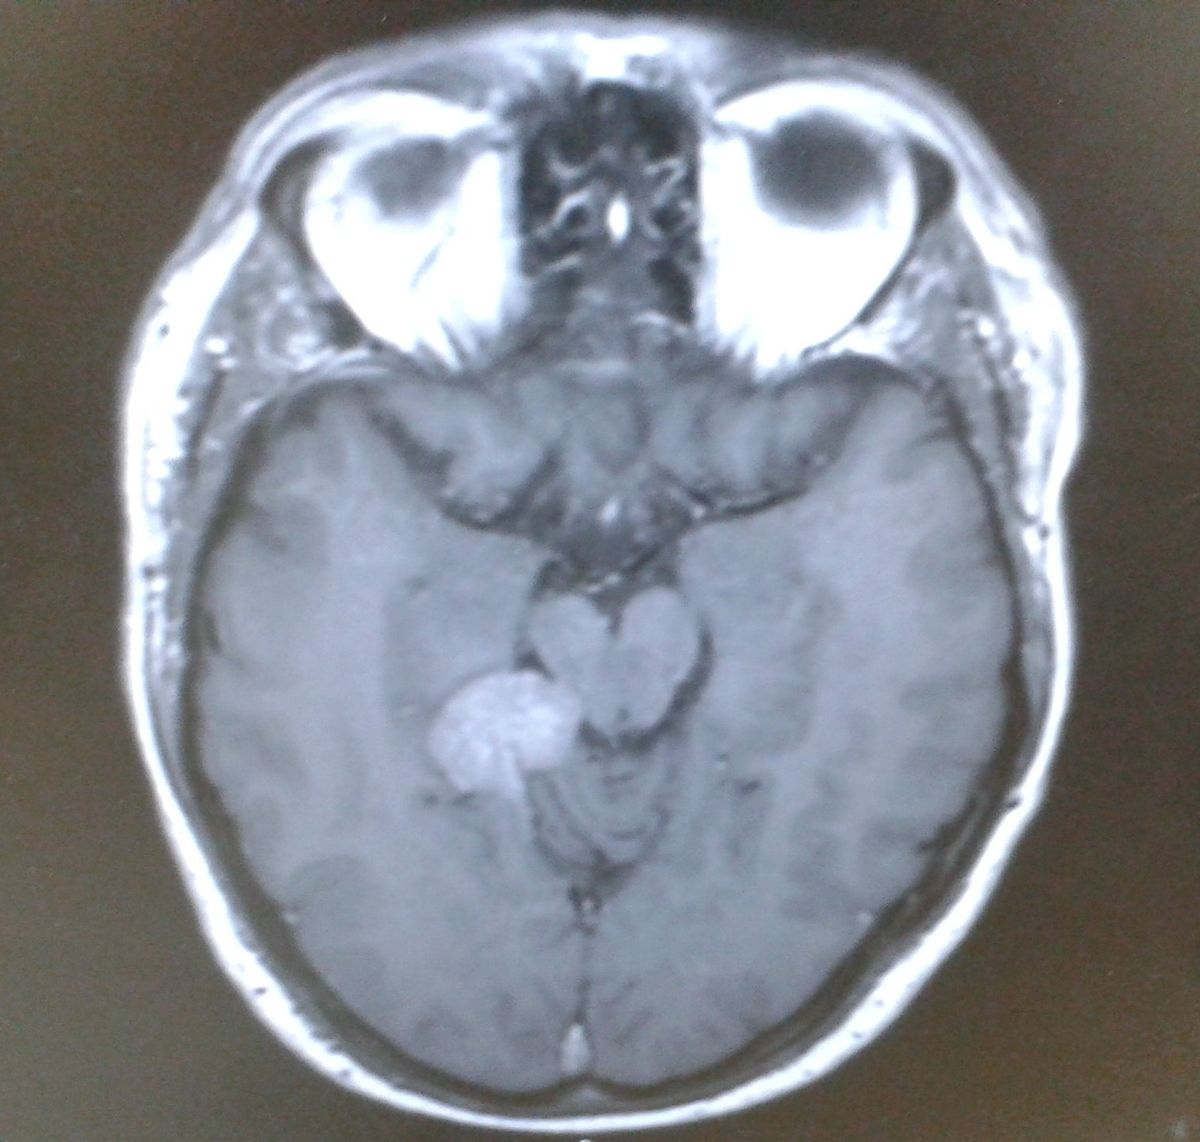

READ MORE: NHS GP urges people ‘stop brushing off’ these symptoms as ‘cases surge’READ MORE: ‘We never thought we’d hear our daughter laugh again – it’s a Christmas miracle’A scan of Darren's head showing his brain tumourMedics found a brain tumour(Image: Brain Tumour Research / SWNS)

In March 2015 it turned out that Darren had a very serious brain tumour which was only treatable using a highly specialised “cutting edge” technique that cost £35,000. This was gamma knife radiosurgery, and sounded like something out of a dystopian science fiction film.